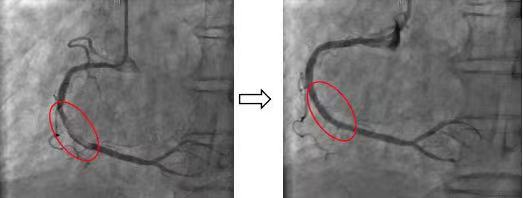

其中一名患者为老年男性,既往有间质性肺病等肺部基础病,此次因为发热伴有呼吸困难来院就诊,诊断为新冠病毒感染导致肺炎并伴有呼吸衰竭。然而,老先生同时突发剧烈胸痛,心电图诊断为急性下壁心肌梗死。患者病情危重,急诊立即为患者行无创呼吸机治疗,同时洽心血管中心启动心梗抢救绿色通道,心脏内科副主任医师周博达火速赶往急诊接诊,导管室团队同步启动接台准备。

急诊冠状动脉介入术中,手术团队迅速锁定患者右冠脉内大量血栓,为患者进行了冠状动脉内血栓抽吸术、冠状动脉内球囊扩张术,并顺利植入一枚最新一代药物洗脱支架。术后患者的胸痛症状立即缓解,收入心脏内科重症监护室进行后续治疗。

患者影像